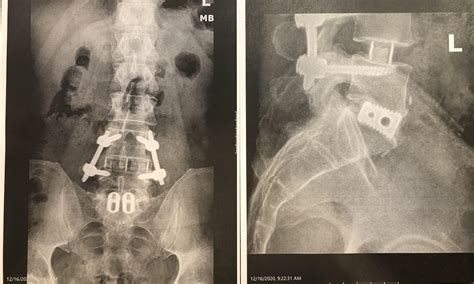

• Instrumentation: Screws, rods, or cages may be used to stabilize the vertebrae and hold them in place while the fusion heals.

• Closure: The incision is closed with sutures or staples, and the patient is taken to the recovery room.